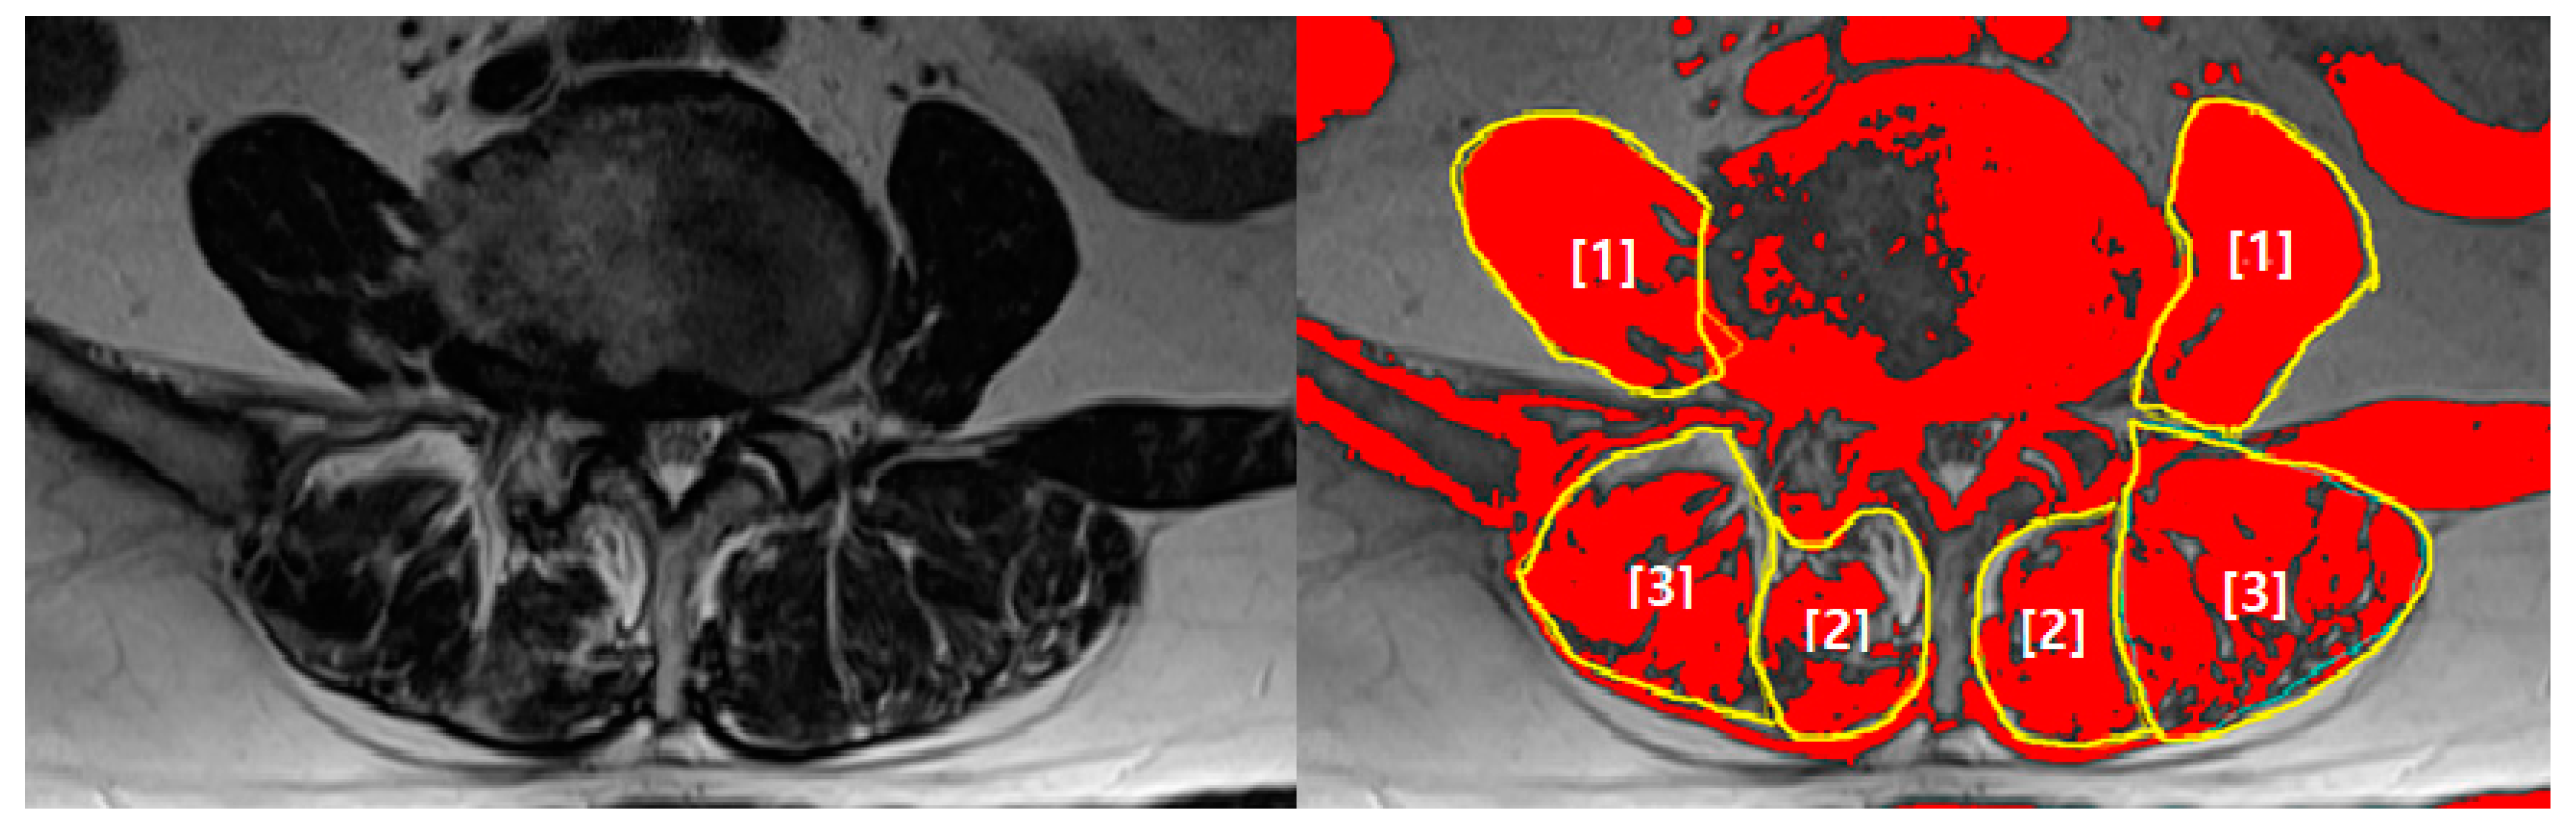

2.2. Measures and Procedures